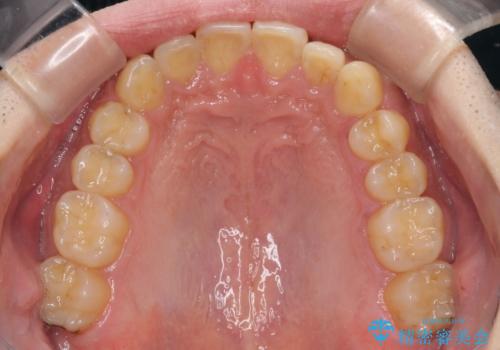

- 上下前歯のデコボコと下の前歯が隠れるほどの深い咬み合わせを気にして来院された患者様です。

インビザラインによる上下歯列の拡大と、IPR(歯と歯の間を削る)にるスペースの獲得により、口元のデコボコとディープバイトを改善することとしました。

デコボコがなくなったことで日頃の清掃が行いやすくなり、深い咬み合わせが改善したことで、食いしばりによる顎の負担も軽減されました。